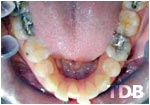

Avant et après Invisalign®

Avant usage d’Invisalign

Après usage d’Invisalign